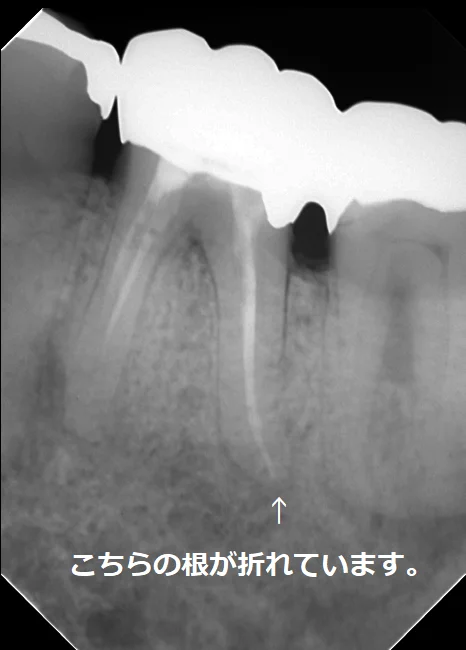

こちらの方は私が治療に入った時にはファイバーコアが入っていましたが・・・

その前は太いメタルコアが入れられていたそうです。

実際に被せ物を除去して根の状態を直接肉眼で確認したところ、後ろ側の根がレントゲンには写らないラインで真っ二つに折れていました。

今回の場合も2本の根の管があるように最初のレントゲン上では写っていましたが、実際にはその2本は非常に細い道でつながっており、しかも元々の根の管がその細い道の中に隠れていました。

最初のレントゲンに比べると神経の治療後の薬が根の先まで綺麗に入っているのが分かるかと思います。